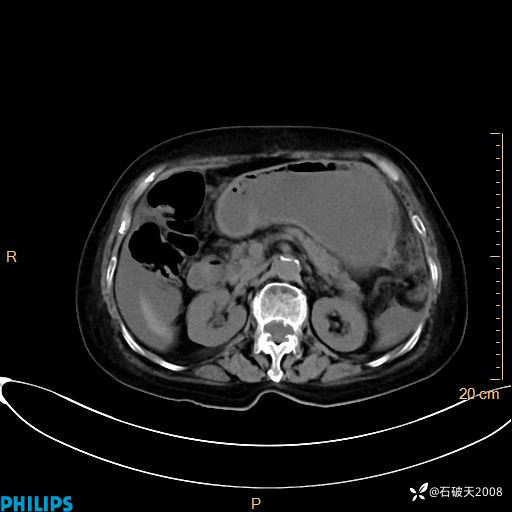

动脉期